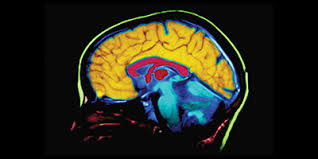

Clínica de neurociencias y neurorehabilitación

neurorehabilitación

Somos un equipo de profesionales de la salud mental enfocados en la atención clínica de la neurorehabilitación

Integramos procedimientos de Evaluación, Diagnóstico y Tratamiento con Metodologías y Tecnologías en Biofeedback, Neurofeedback y Estimulación Magnética Transcraneal (EMT) para afecciones en los campos de:

NEUROREHABILITACIÓN

Recupera funciones perdidas y mejora tu calidad de vida con nuestras terapias especializadas.